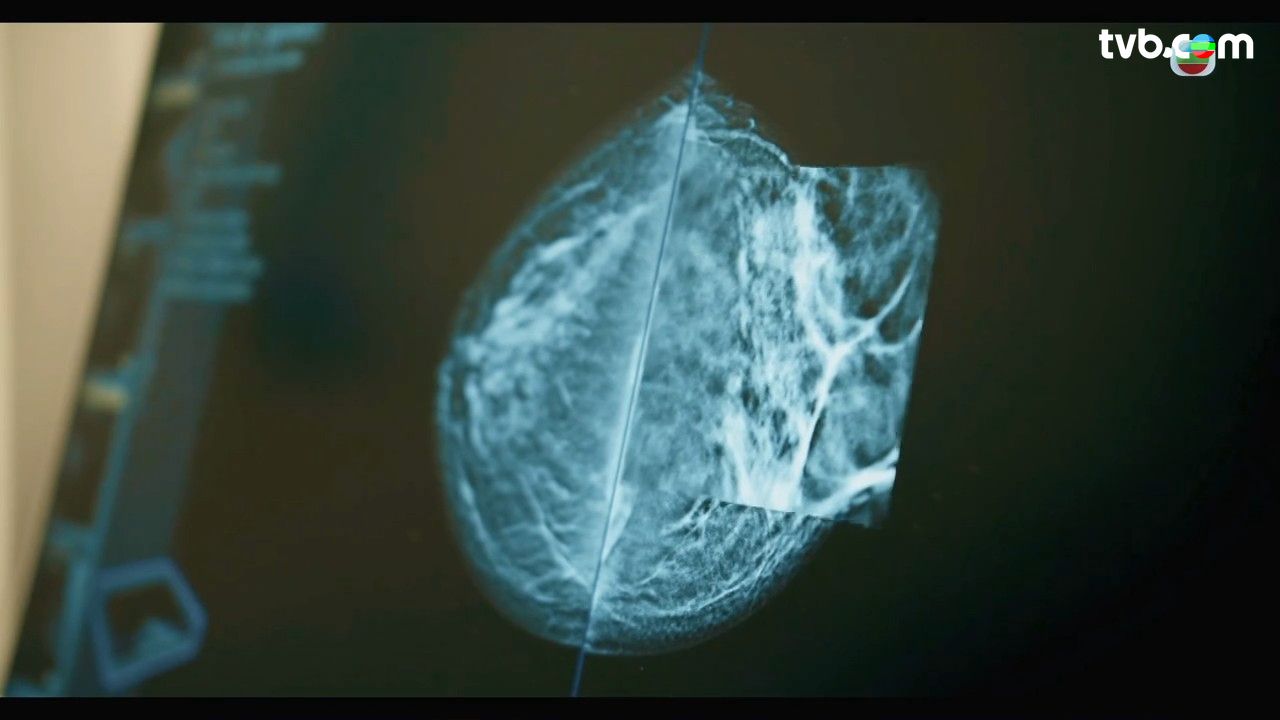

乳房檢查包括觸檢、超聲波、造影和抽針檢查等,醫生解釋有時乳房造影報告可能都難以發現乳癌。施俊健醫生指,有些患者可能乳腺密度比較高,會令乳房造影未必看得太清楚,常見是亞洲女士。